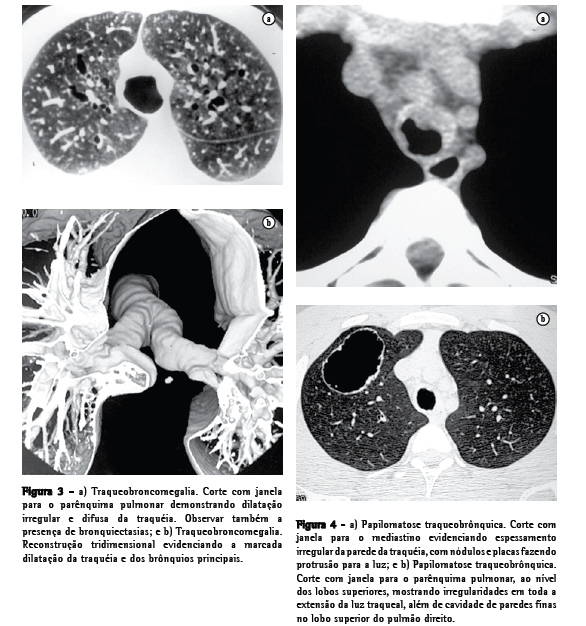

Amiloidose Traqueobrônquica

A amiloidose é caracterizada pela deposição, local ou sistêmica, de material amilóide anormal em tecidos extracelulares, podendo envolver múltiplos órgãos como o coração, os rins e o trato gastrointestinal, entre outros.(3-5) A amiloidose respiratória primária apresenta três formas características: a nodular, a parenquimatosa difusa e a traqueobrônquica.(3-6) A mais comum é a traqueobrônquica. Os sintomas mais freqüentes incluem tosse, dispnéia, hemoptise e rouquidão.(4) O achado radiográfico predominante é o estreitamento nodular e irregular da traquéia. A TC computadorizada (TC) pode mostrar nódulos fazendo protrusão na luz traqueal ou ainda, mais comumente, mostrar espessamento parietal difuso, com placas submucosas multifocais(5,7) (Figura 1). Ao contrário do que acontece na traqueobroncopatia osteocondroplástica, a parede posterior da traquéia pode estar comprometida. A parede espessada pode apresentar calcificações.(6,7) Alterações parenquimatosas secundárias à obstrução brônquica do tipo colapso podem ser vistas, assim como consolidações infecciosas recorrentes, bronquiectasias e hiperinsuflação obstrutiva.(3,7)